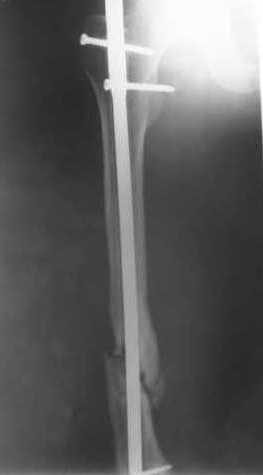

Пациенту М., 30-ти лет, 1,5 года назад в одной из московских больниц был выполнен остеосинтез бедренной кости штифтом UFN (диаметр штифта 9 мм).

К нам больной поступил с признаками ложного сустава бедренной кости, перелома

штифта и дистального блокирующего винта (images 1,2,3).